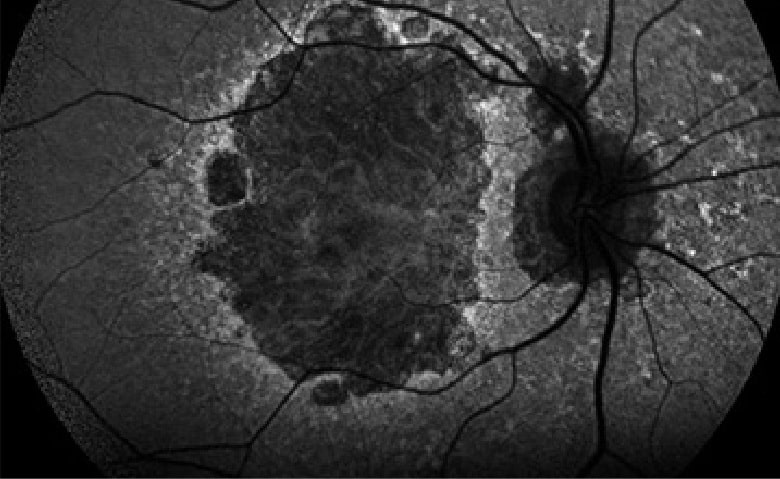

Autofluoresceína

Las imágenes de autofluorescencia del fondo del ojo son una técnica no invasiva que proporciona información detallada del surgimiento y evolución de enfermedades retinianas complejas y hereditarias como por ejemplo la DMAE. Proporciona por tanto información sobre la fisiopatología de la enfermedad y permite comprender la naturaleza de las enfermedades maculares y retinianas para que el oftalmólogo realice diagnósticos más exactos.